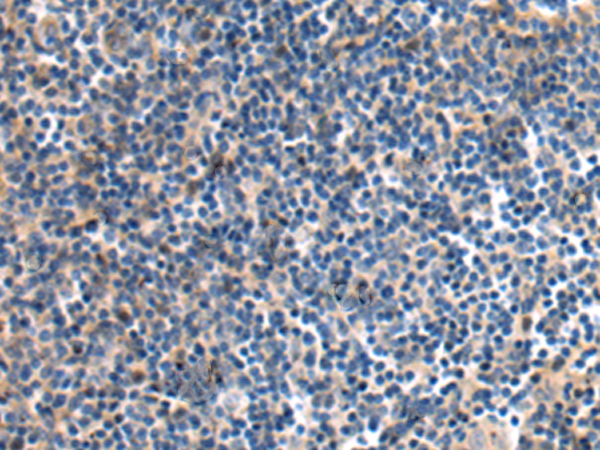

分类: 科研抗体货号: P10600别名: FAKTS; URLC9; hFLEG1应用: IHC反应种属: Human